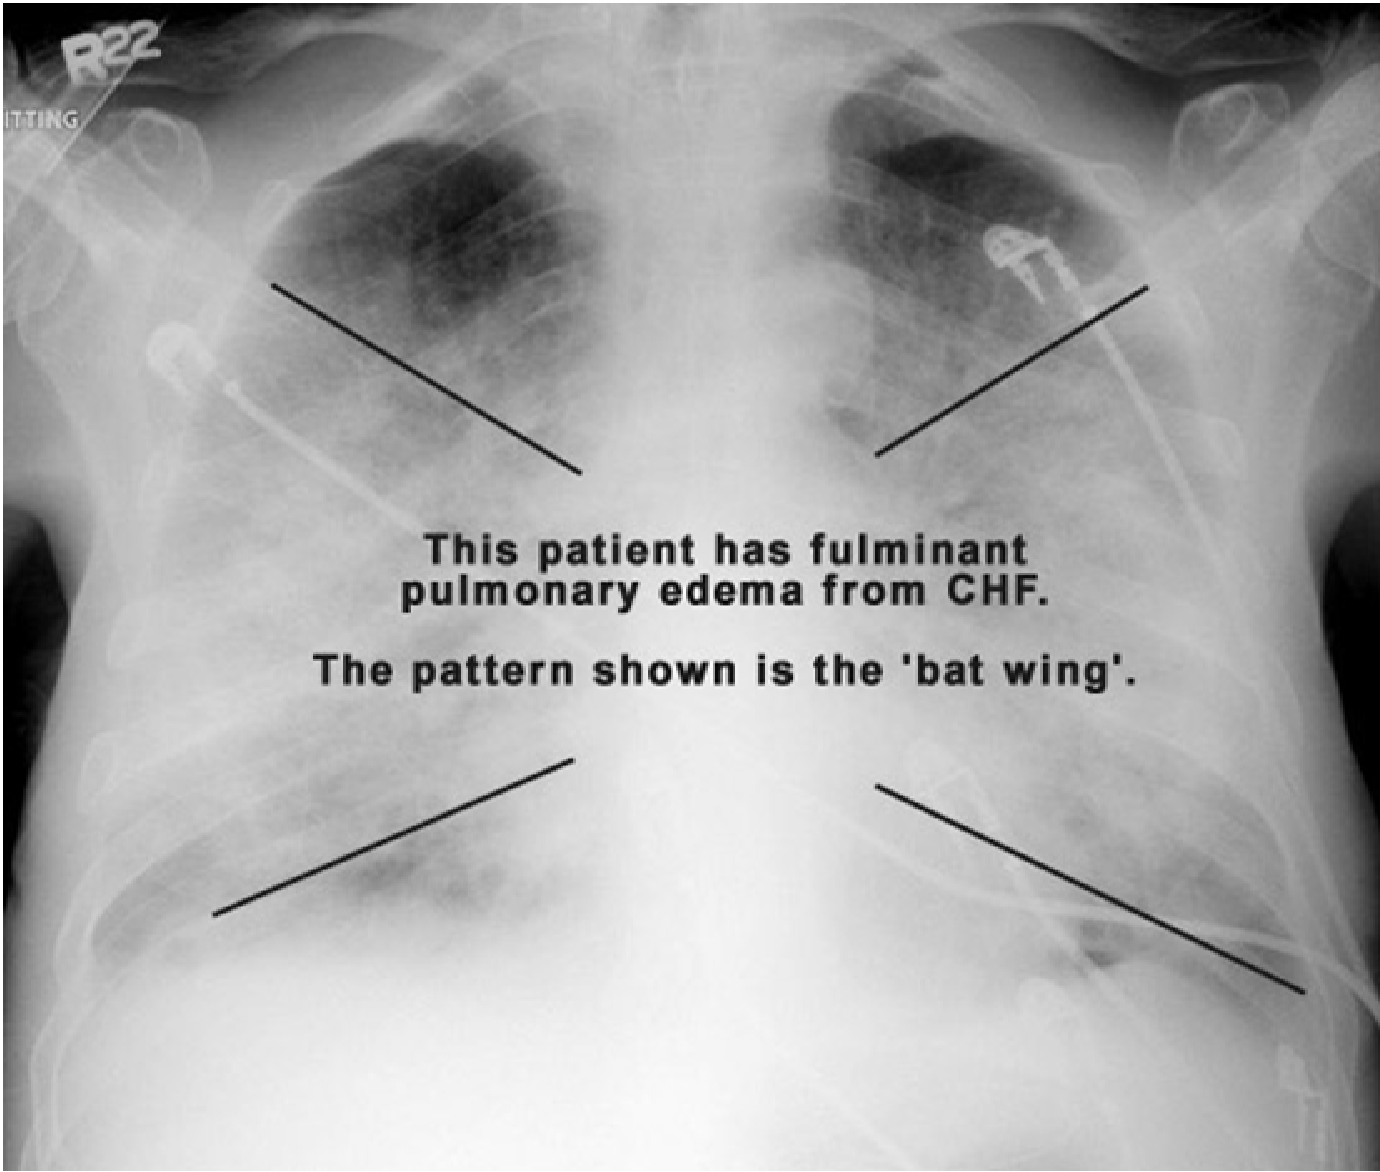

Pulmonary Edema Chest X Ray Chest X Ray Findings Pulmonary Hypertension Further imaging such as ct can identify diseases of the lung parenchyma. Pah may present with central pulmonary arterial dilatation, ‘pruning’ of peripheral vessels, right atrial and ventricular enlargement (later stages). The reported causes were ph, congenital heart disease (overcirculation lesions such. This paper also provides concrete definitions, wherever possible, of what constitutes abnormalities in ph, such as dilated pulmonary. Chest X Ray Findings Pulmonary Hypertension.